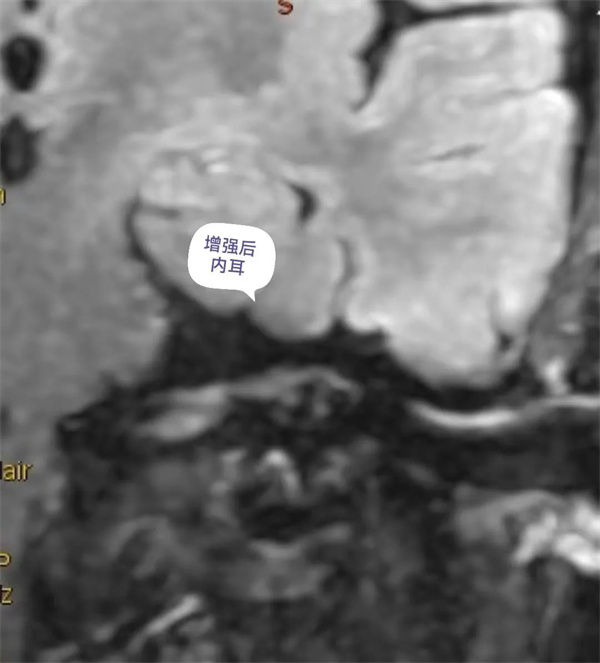

圖12:增強后內(nèi)耳外淋巴液磁共振顯示圖。